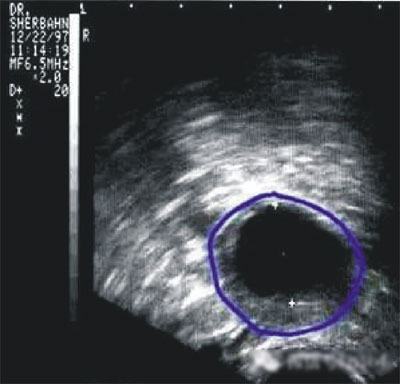

第三步:排卵監(jiān)測(cè)

常用的監(jiān)測(cè)排卵方法有基礎(chǔ)體溫測(cè)定(BBT)、陰道B超監(jiān)測(cè)排卵、血清性激素測(cè)定等。

陰道B型超聲動(dòng)態(tài)監(jiān)測(cè)卵泡的發(fā)育及排卵,是監(jiān)測(cè)排卵最準(zhǔn)確可靠的方法。通過陰道B超檢查可以了解子宮及雙側(cè)附件(卵巢和輸卵管)區(qū)的基本情況,測(cè)定卵巢內(nèi)的竇卵泡計(jì)數(shù),評(píng)估卵巢儲(chǔ)備功能,動(dòng)態(tài)監(jiān)測(cè)排卵。